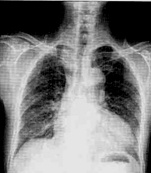

| 病史:男性,65歲,活動后胸悶6個月。既往高血壓病史15年。診斷: |

| ○ 靴型心 | |

| ○ 梨形心 | |

| ○ 普大型心臟 | |

| ○ 正常心臟 | |

| ○ 以上均不是 |